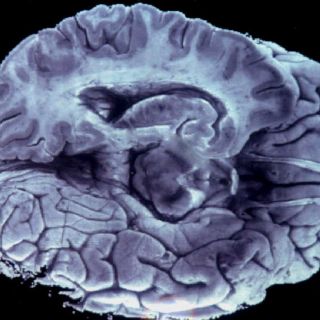

CIUDAD DE MÉXICO (08/ENE/2013).- Una nueva esperanza para quienes sufren de migraña han abierto científicos de la Universidad de Michigan, en Estados Unidos, al revelar una posible cura a través de pequeños y controlados choques eléctricos.

El descubrimiento beneficia a quienes padecen de migraña crónica, toda vez que esta terapia, denominada estimulación cerebral profunda, reduce al dolor de la cabeza hasta 37 por ciento.

De acuerdo con una publicación del sitio en Internet en español RT, esta técnica que aplica una corriente eléctrica de dos miliamperios, modifica la velocidad con la que las neuronas reciben un estímulo y dirigen los impulsos nerviosos, y sirve para aliviar el dolor.